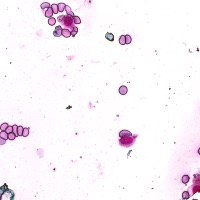

Medical Diagnosis: The "4class" model can be employed by pathologists to accurately identify and quantify the different cell types in blood and tissue samples, assisting in the diagnosis of various blood disorders and diseases, including anemia, leukemia, and infections.

Research and Drug Development: Researchers can use the "4class" model to analyze cellular response to experimental treatments, providing essential data for drug discovery, evaluating the efficacy of novel compounds, and understanding cell behavior under various conditions.

Education and Training: The "4class" computer vision model can serve as an educational tool for medical students and professionals, facilitating their understanding of different cell types, their characteristics, and functions, while promoting accurate identification in laboratory settings.

Automated Screening: Integration of the "4class" computer vision model into medical laboratory equipment can automate the process of cell classification during screenings or biopsies. This can help save time and reduce the risk of human errors during the evaluation of samples.

Telemedicine and Remote Analysis: The "4class" model can support telemedicine platforms, making it possible for healthcare professionals to remotely access and evaluate blood and tissue samples. This would be particularly useful in underserved areas, where access to pathologists might be limited.